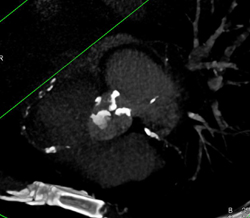

Calcified Bicuspid Valve